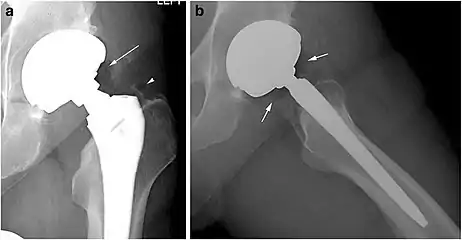

Pneumarthrosis is the presence of air in a joint. Its presentation on radiography is a radiolucent cleft often called a vacuum phenomenon, or vacuum sign.[7] Pneumarthrosis is associated with osteoarthritis and spondylosis.[8]

Pneumarthrosis is a common normal finding in shoulders[7] as well as in sternoclavicular joints.[9] It is believed to be a cause of the sounds of joint cracking.[8] It is also a common normal post-operative finding at least after spinal surgery.[10] Pneumarthrosis is extremely rare in conjunction with fluid or pus in a joint, and its presence can therefore practically exclude infection.[8]

X-ray of a hip with hip replacement and pneumarthrosis, in this case aseptic.

A vacuum sign, or vacuum phenomenon, is a normal finding on shoulder X-rays.